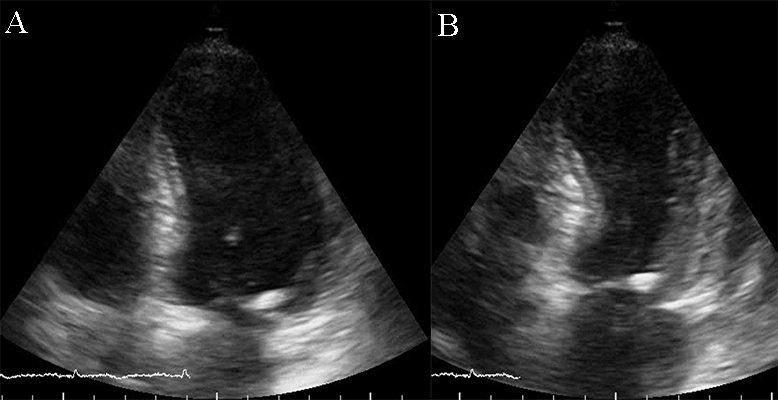

Restrictive cardiomyopathy (RCM) is characterized by non-dilated ventricles, mild or no myocardial hypertrophy with impaired ventricular filling, thus it is defined by abnormal ventricular diastolic function with a normal size LV (see Fig. 8). In the early stages of the disease, the systolic function of the LV is also normal [38].

Fig. 8.The echocardiographic aspect of RCM in an elderly patient presenting with signs and symptoms of heart failure. Apical 4 chamber view showing severe biatrial enlargement, with left atrial thrombus and non-dilated left and right ventricles.